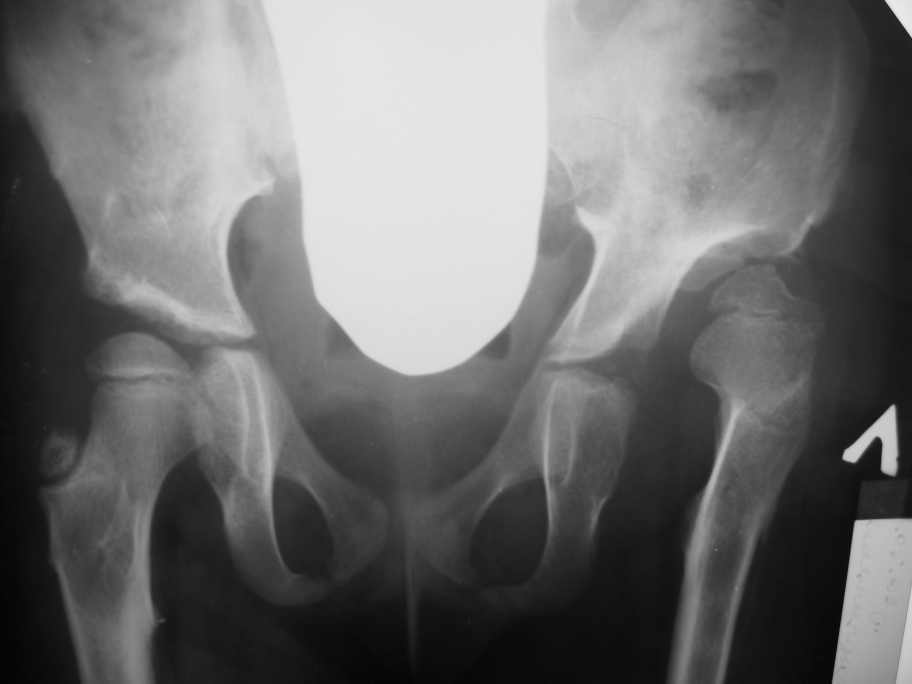

Здравствуйте, уважаемые коллеги. Обратилась девочка 6-ти лет из жалобами на боль в левом т/б

суставе,хромоту. С анамнеза : ребенок лечился с рождения по поводу врожденного вывиха

бедер.В возрасте 3- х лет ,в одной из клиник, была выполнена остеотомия таза по Пембертону и

варизирующая остеотомия бедра слева, справа -остеотомия таза по Солтеру и остеотомия

бедра. Посоветуйте тактику лечения. С уважением Ihor